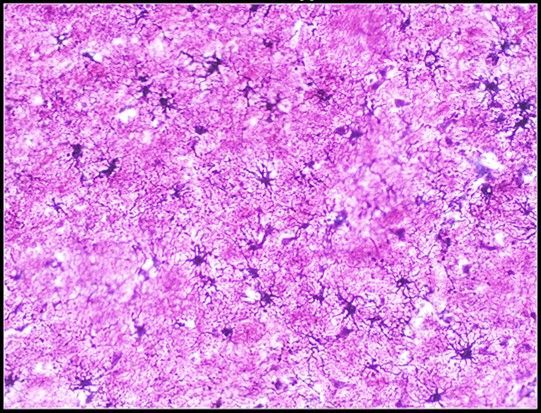

Question 11

Question

Label this Image First Dot: Name Second Dot: Staining

Image:

b9f98ebf-c5d1-42f7-8292-242f9bdaf7c7 (image/jpeg)

Answer

Protoplasmic Astrocytes

AgNO3